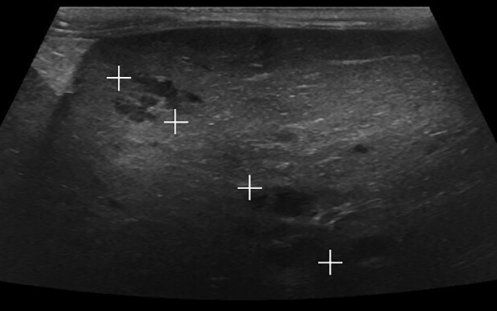

초음파 소견에서 주의 깊게 생각해 볼 문제가 있다.

이런류의 비특이적인 cyst가 무증상 환자에서도 종종 관찰되곤 하는데 이들에 대한 검사가 필요할 수 있다는 사실을 염두에 둬야 한다. 또한 증상이 없더라도 모니터링을 통해 변화 양상을 확인할 근거가 된다.